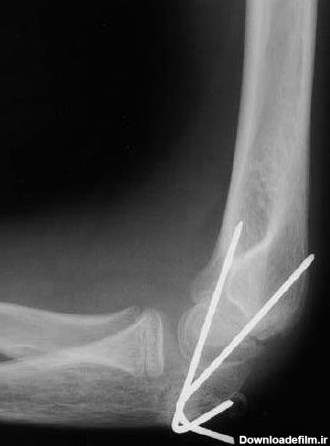

عکس رادیولوژی آرنج سالم کودک

رادیولوژی استخوان بازو باید در دو نمای قدامی-خلفی و جانبی انجام شود و مفاصل شانه و آرنج را نیز در بر می گیرد.عکس رادیولوژی مفصل آرنج شامل..